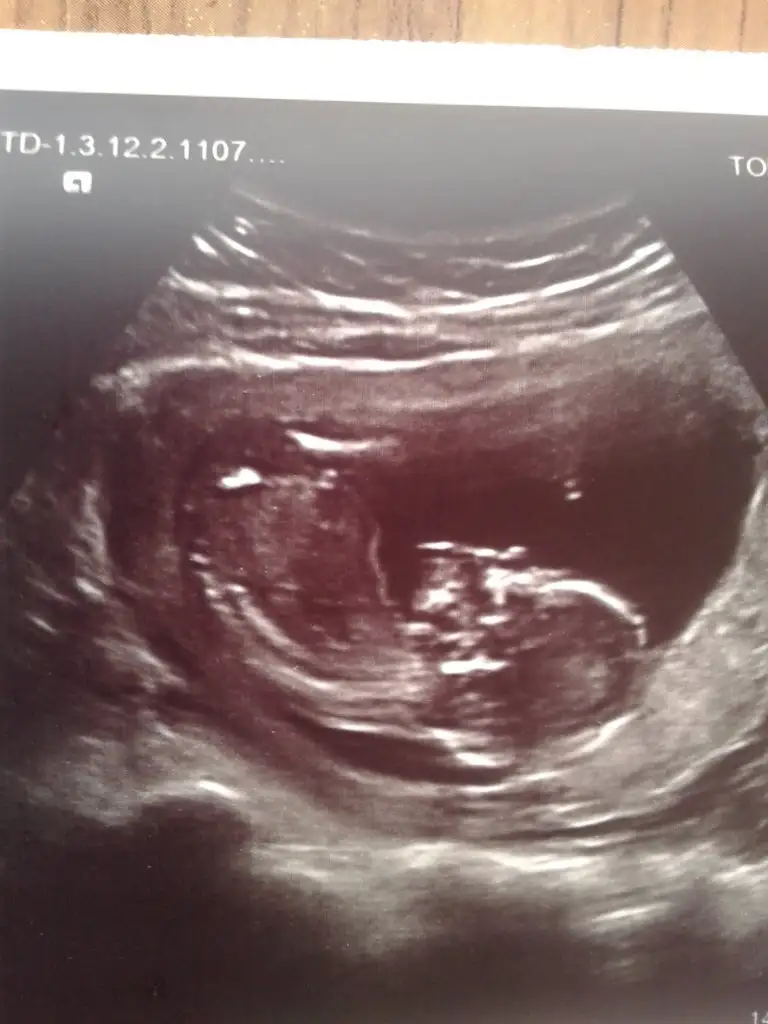

bu da diger acidan fotografi ayagi kapatmis gibi amabu bu haftaki goruntusu 12. hafta gecen hafta erkek demistiniz ama emin olamamistiniz@ikrameyra

Mrb 13 haftalik olduk cok sukurKız gibi net de değil kız sanki 12-13 olunca tekrar usg paylaşın

Kız gibiMrb 13 haftalik olduk cok sukur

Kız gibi